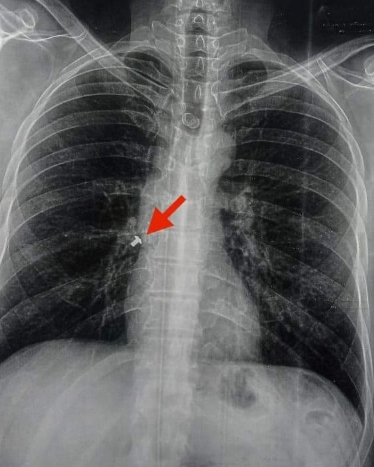

تمكن فريق طبي بمستشفى بنها الجامعي، برئاسة الدكتور محمد الجزار استاذ واستشاري طب مناظير وجراحة الصدر بطب بنها، من إنقاذ حياة كهربائي ابتلع مسمار أثناء تركيب كشاف سقف فاستقر في القصبة الهوائية مباشرة.

وأوضح الدكتور محمد الجزار، أن الجراحة تعد الأولى لاستخراج مسمار، من القصبة الهوائية لشاب وليس طفلا ويكون ابتلعه رغما عنه، مشيرا أن الشاب حالته مستقرة ويخضع للملاحظة داخل مستشفى بنها الجامعي.